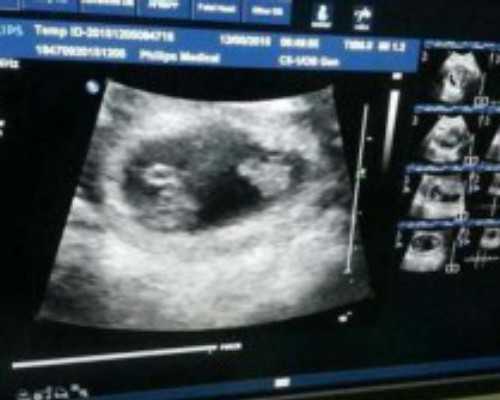

广州供卵试管代怀生子医院排名,附供卵生男孩费用一览!我想问问最晚几天能着床啊?囊胚已经是胚胎发育的最终形态了,所以一般当天就能够进行移植,并且移植后着床的速度也是非常快的。5天囊胚一般在移植当天就能开始着床,但是也需要几天的时间才能够完全着床。通常情况下,5天囊胚在移植后1-2天就会开始着床,4-5天就能够着床成功,最晚不会超过7天。冻胚有第三天的卵裂期胚胎也有第五天的冻囊胚,其实移植后着床的时间相差不大,至于最晚几天着床,几天可以测出来说不准。有部分患者最晚在移植后第14天验孕成功,也有部分患者可能会延迟一两天,具体最晚多久可以查测出来,其实与胚胎的子宫环境、患者的年龄、胚胎质量息息相关。移植4bb囊胚的成功率很高